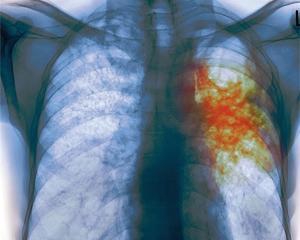

В Украине вылечиваются лишь 55-59% больных туберкулезом. Это значит, что лечение проходит неэффективно.

Она объяснила, что от обычного туберкулеза человек лечится первым рядом медикаментов в течение 6-ти месяцев. В течение 2-3 месяцев она лежит в тубдиспансере, остальное время принимает лекарства дома.

"Тогда люди часто чувствуют себя легче и бросают лечение. Но недолеченный туберкулез становится мультирезистентным. Эту форму лечить намного тяжелее. Во-первых, это занимает 18-24 месяцев, во-вторых, человек должен пить более тяжелые препараты - так называемые лекарства второго ряда. А государство обеспечивает ими лишь на 40%, тогда как лекарств первого ряда закупают почти на 100%. Чтобы человек не бросал лечения туберкулеза и не ухудшал состояние собственного здоровья, со следующего года мы организуем раздачу пайков для больных туберкулезом. Этим мы будем мотивировать людей приходить и получать лекарства", - сообщила Билык.